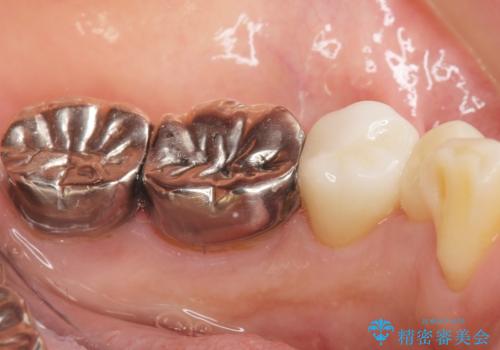

セラミッククラウンの自然な仕上がりと咬み心地に大変ご満足頂けました。

歯がしみる症状もなくなり、外側に出ていた歯が気にならなくなったと喜んで下さいました。

クラウンの種類:オールセラミッククラウン エコノミー